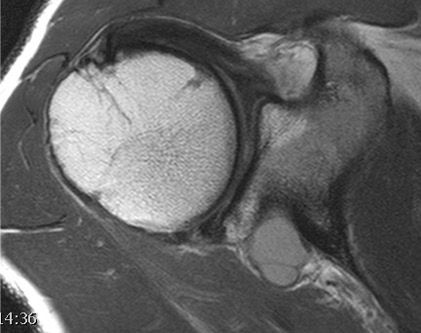

MRI

Posterior labral tears / bankart lesion

Posterior labral tear

Posterior labral tear